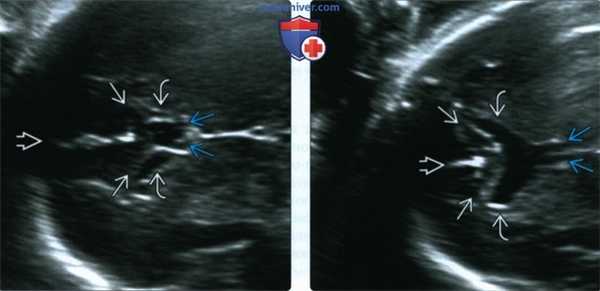

(Слева) На увеличенном изображении нормально сформированного переднего отдела у плода на 30-й неделе гестации визуализируются межполушарная борозда, передняя часть мозолистого тела (колено), свод головного мозга и ППП в форме коробки между передними рогами боковых желудочков.

(Справа) На аналогичном изображении переднего отдела у другого плода видны межполушарная борозда, передняя часть мозолистого тела (колено) и раздельные столбы свода мозга ППП, которая должна находиться между передними рогами в отсутствует. При рождении ребенка была констатирована СОД.